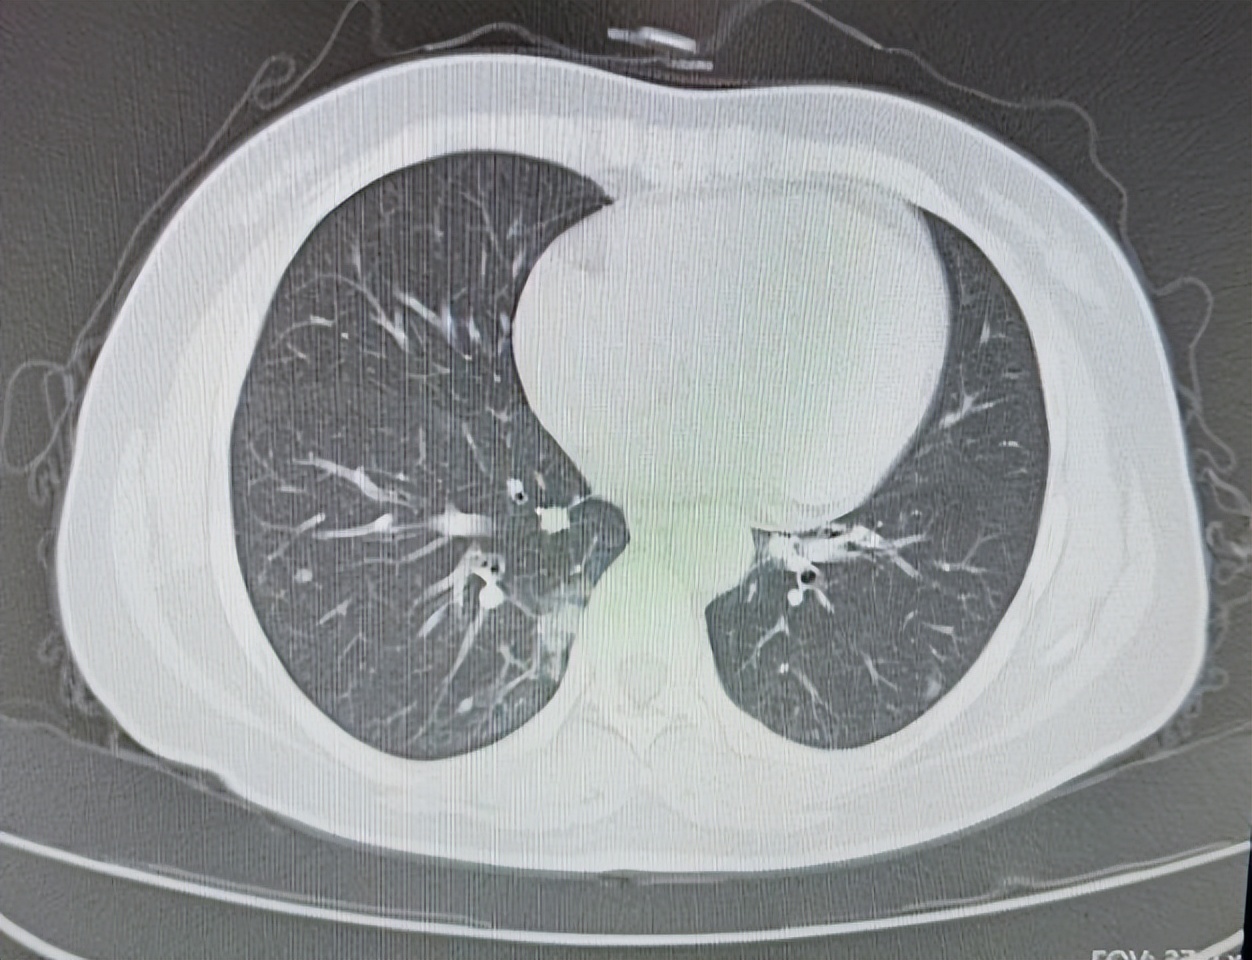

大爷姓李,2018年底无明显诱因出现间断咳嗽咳痰,受凉后加重,在我们医院诊断为慢性阻塞性肺病肺气肿慢性支气管炎,对症治疗后有所好转,其后定期复查,2019年6月在医院做胸部CT检查发现右肺有阴影。PET- CT检查提示,双肺多发结节及类结节影,部分结节葡萄糖代谢增高,考虑结核等肉芽肿性病变。

当时患者没在意,后来又在我们医院做胸部增强CT提示,右肺下叶背段占位考虑恶性,建议穿刺,纵隔及右肺门区多发肿大,淋巴结考虑转移可能性大。

2020年1月,在CT引导下,肺主穿刺活检病理提示肺组织中可见肿瘤细胞呈巢团状排列,细胞有异型性,考虑为 肺腺癌 。

图片来源 :讲述者提供